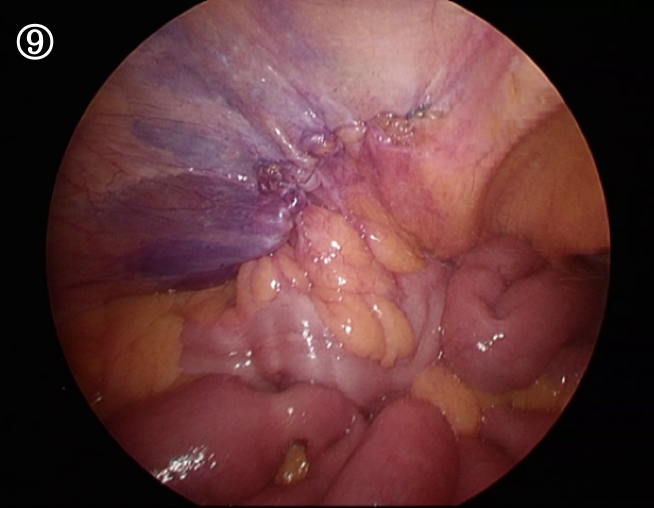

腹膜をまたもとの状態に戻します。隙間があると腸が入り込むので、ぴっちりと縫い合わせます。

完成です。隙間なく腹膜が覆えているのが分かると思います。